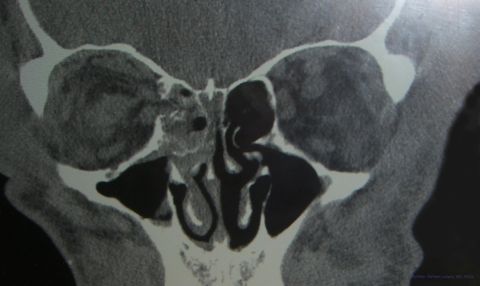

Radiologic studies, generally a CT, would confirm the presence of a medial orbital fracture. Plain films are not recommended for medial wall fractures as they detect less than 50% of the fractures, give less detail than CT and still utilize radiation. MRI is never the first line imaging after trauma (given concern for an unknown metallic intraocular foreign body) and provides less bone detail than CT. The CT should be evaluated in detail to rule out a concomitant Naso-Orbito-Ethmoid (NOE) fracture.

Computer tomography (CT) is the primary diagnostic tool in evaluating for orbital fractures, muscle entrapment or retrobublar hemorrhage. In addition, CT can help in assessing the size of fracture and plan subsequent surgical repair. While plain film x-rays of the orbit may reveal an ethmoidal sinus opacity, the test is insensitive in detecting medial wall fractures.